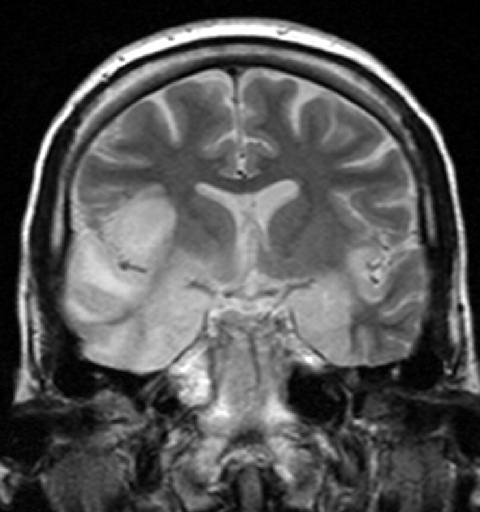

МРТ женщины 33 лет с герпетическим поражением мозга

Одним из наиболее грозных проявлений вируса герпеса является герпетический энцефалит.

Вирус при этом мигрирует по аксону тройничного нерва в головной и далее активно развивается, преимущественно в височных долях. У пациента при этом резко поднимается температура, начинаются эпилептические припадки и другие неврологические симптомы.

Течение тяжёлое, а впоследствии часто развивается деменция. К счастью, это довольно редкая история с рисками в районе 1:500 000.